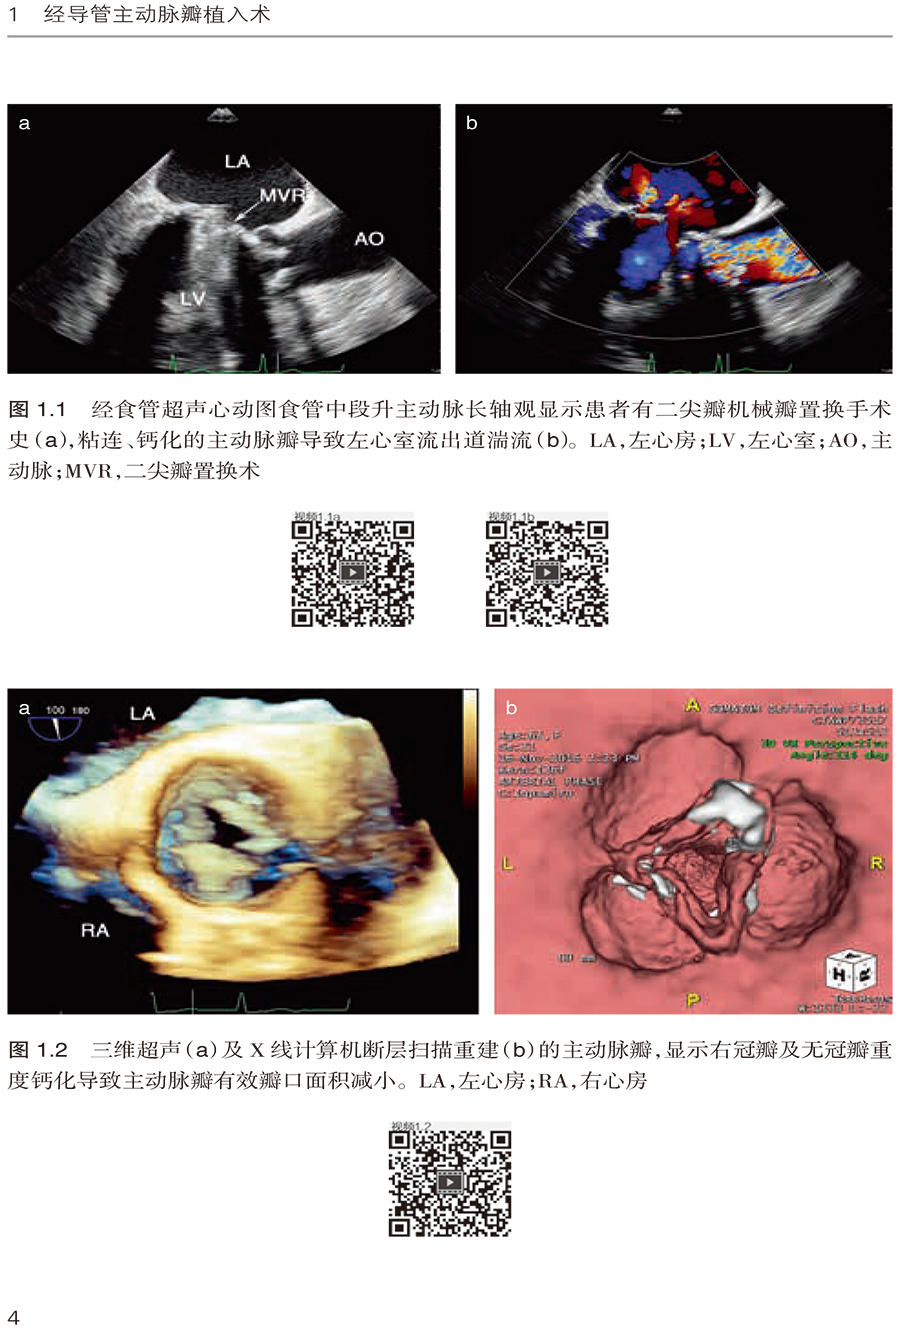

1.2 经心尖SAPIEN 瓣膜植入术 /3